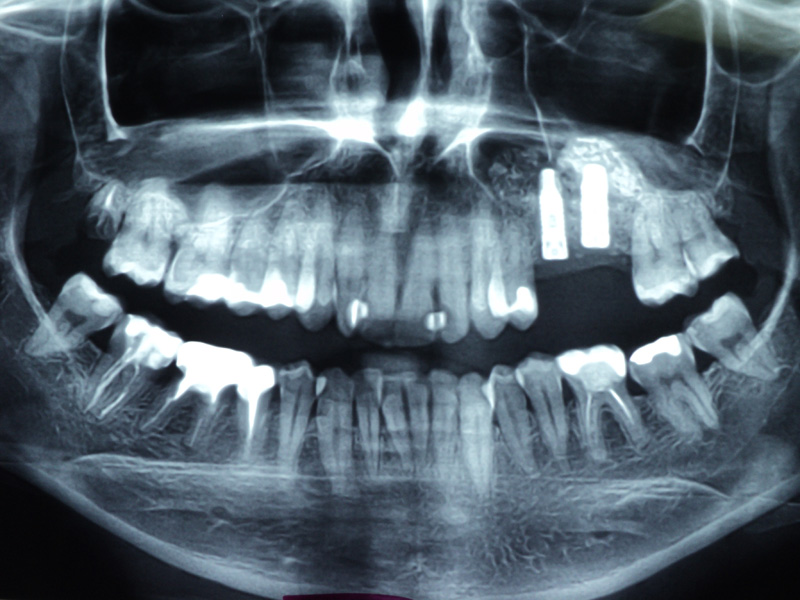

Implante - Galerie Foto

Caz IV